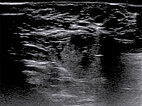

To confirm the diagnosis, an ultrasound-guided punch biopsy was now taken from the lesion on the right labium majus using a 16-gauge disposable biopsy gun. The biopsy needle advanced into the lesion produces strong distal acoustic shadowing on B-scan imaging.